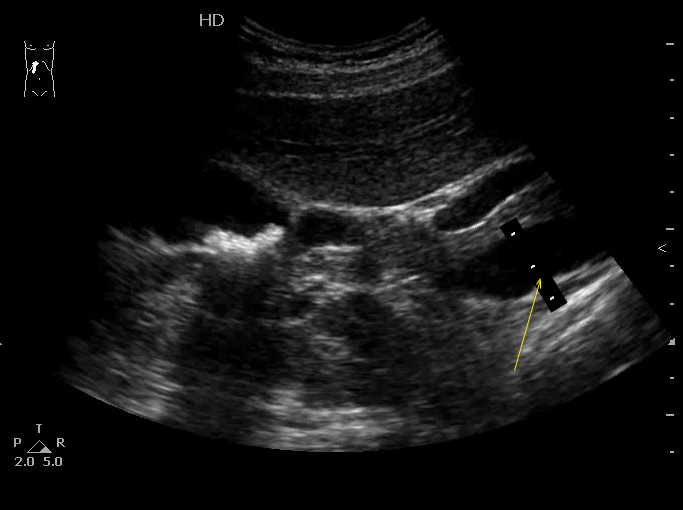

УЗИ ЖВП: конкремент в пузырном протоке

Молодая женщина, плановое обследование.

Жалоб не предъявляет.

Ваше заключение?

ЖКБ, холецистолитиаз, необструктивный конкремент пузырного протока.

Оперирована, все подтвердилось.

Да, холедох где то до 7-8 мм. - верхняя граница нормы.

Камни в пузырном протоке четко видны.